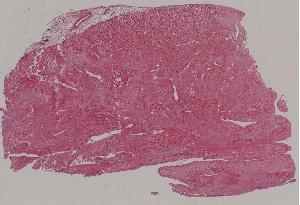

8. Granulation tissue